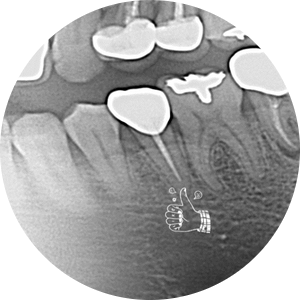

오른쪽 위 어금니 충치가 심해서 발치를 하자고 했었는데 미루시다가 이제는 너무 불편해서 안되겠다고 당분간 일을 쉬게 되어서 여유있게 다른 치료도 받고싶다고 하셨다.

원래 발치하기로 했던 치아는 더 썩어서 부러져 있어고 좌측 아래 작은 어금니도 그동안 충치가 많이 진행되어 신경치료가 필요한 상황이었다.

그래도 아직 임플란트 수술까지는 무서워하시니 수술은 다시 수면치료

수술도 잘 끝나셨고 자주 보니 더 친해지고 해서 더 용기내서 잇몸이 많이 부어서 잇몸치료가 필요한데 비수면으로 진행해보자고 말씀드리고 당일 도포마취, 무통마취 내가 할 수 있는 조치는 다 해서 무사히 첫 번째, 두 번째 잇몸치료를 마쳤다...